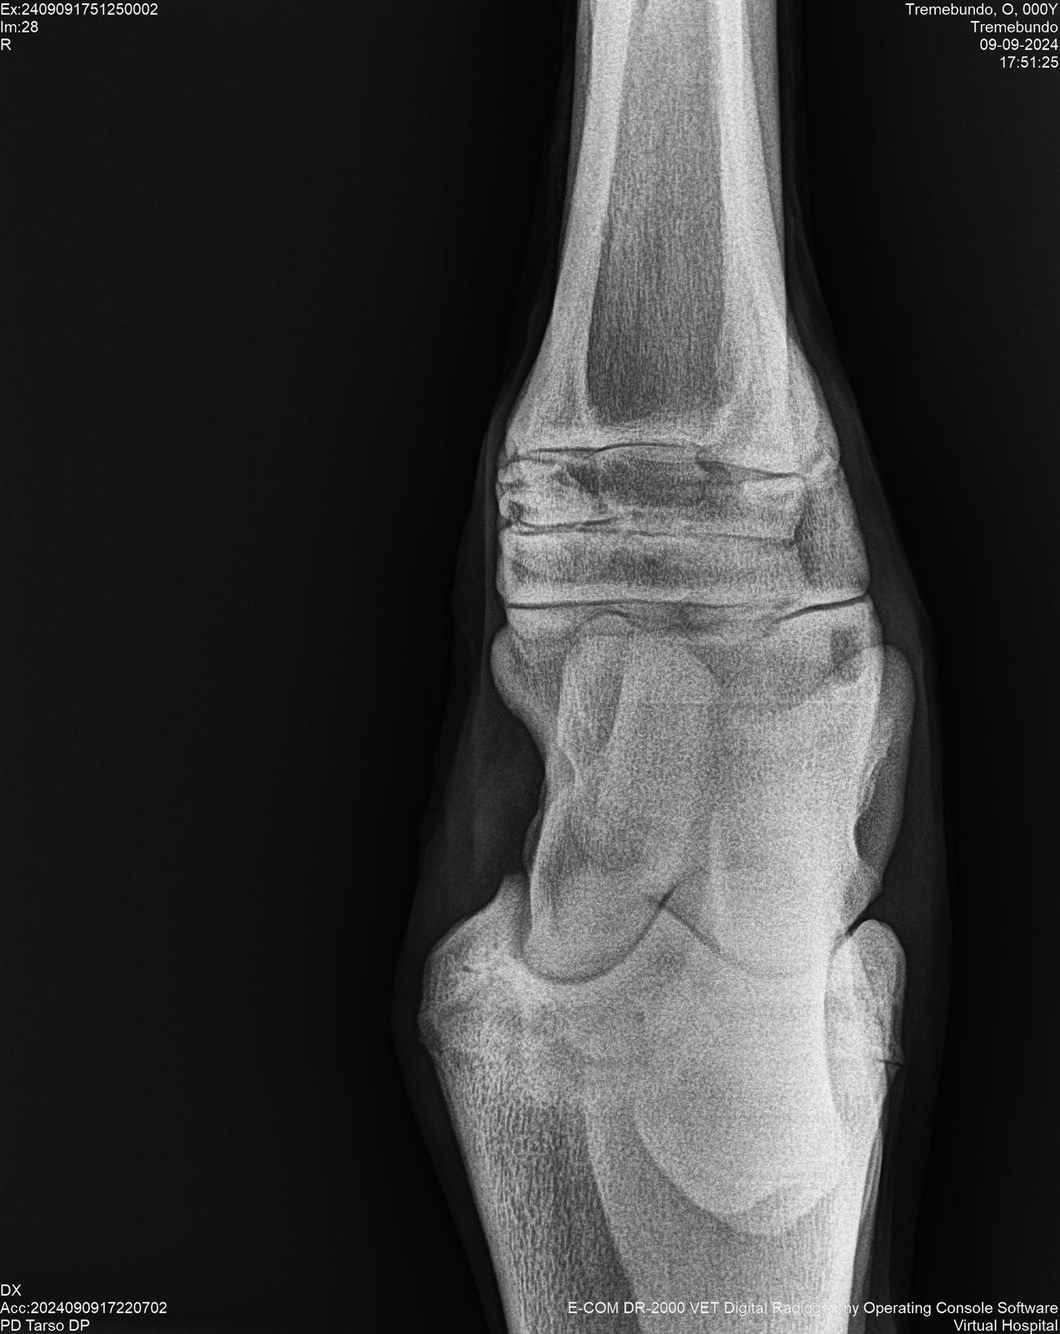

LOTE 37, TREMEBUNDO

Identificador: #291140-

Generacion 2022